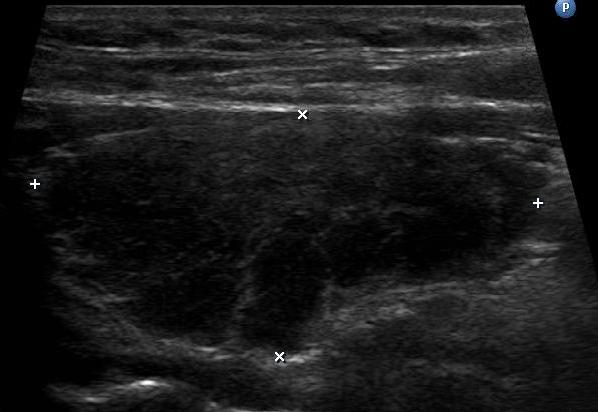

Multinodular goiter is described as numerous nodules in an enlarged thyroid gland caused by a relative iodine deficit.

Multinodular goiters are typically nontoxic (euthyroid).

Rarely, an area will lose its thyroid stimulating hormone (TSH)-dependent state, causing T1 release, hyperthyroidism, or toxic goiter.

Thyroid nodules are more likely to be benign than malignant, and thyroid neoplasia usually appears as a distinct, solitary nodule.

I-131 radioactive uptake studies are useful to further characterize nodules.

Increased uptake (hot nodule) is seen in Graves’ disease or nodular goiter.

Decreased uptake (cold nodule) is seen in adenoma and carcinoma and they often warrant biopsy.

Biopsy is performed by fine needle aspiration (FNA).